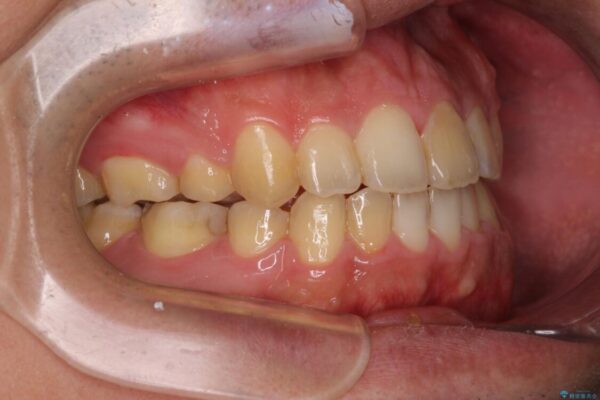

治療途中

• 後戻りでデコボコの前歯 インビザライン矯正治療 治療途中画像